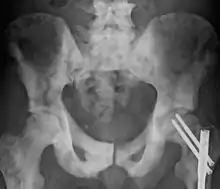

| Sclerosis of the bones of the pelvis due to prostate cancer metastases | |

Osteosclerosis is a disorder that is characterized by abnormal hardening of bone and an elevation in bone density. It may predominantly affect the medullary portion and/or cortex of bone. Plain radiographs are a valuable tool for detecting and classifying osteosclerotic disorders.[1][2] It can manifest in localized or generalized osteosclerosis. Localized osteosclerosis can be caused by Legg–Calvé–Perthes disease, sickle-cell disease and osteoarthritis among others. Osteosclerosis can be classified in accordance with the causative factor into acquired and hereditary.[2][1]